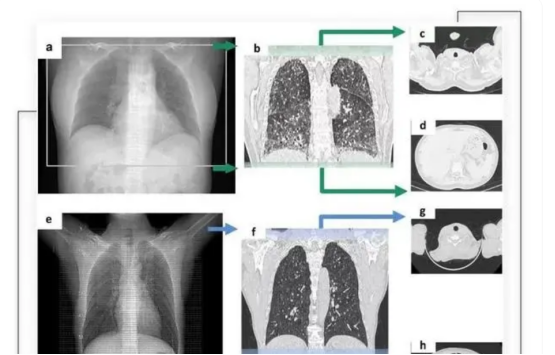

AI医学影像分析,则是利用机器学习、计算机视觉等技术,对医学影像数据进行自动化分析和诊断,并根据大量的定量特征,如形态、纹理、灰度、强度等,与基因、临床等其他数据进行关联分析,发现疾病的生物标志物和预后因素。

通过搭载了智能算法的CT摄像头,将深度学习卷积神经网络与典型的模式识别算法创新地结合在一起,从而精准识别CT扫描范围。

其主要技术,是通过深度学习及卷积神经网络模型,模仿人类认知过程,让AI模型自动挖掘医学图像中的规律。

其AI产品InferOperate,通过对脑电图、脑功能成像等多种类型的神经影像数据进行深度学习,提取影像特征,定位病灶,从而为医生提供智能手术规划、术中全自动定位导航等。